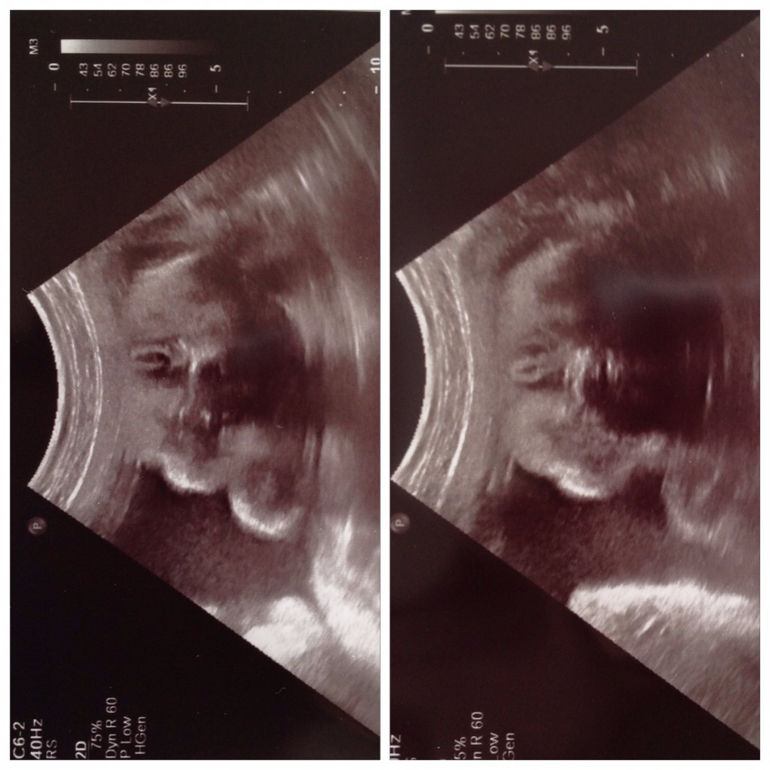

Конечно, посмотрели нашего мальчика. Он так сладко лежал, положив головку на локоть, моргал, и открывал и закрывал ротик. Я готова была на это смотреть весь день, такая это милота была! Вырос до 34 см и весом 1423 грамма)))) это получается за 10 дней он набрал 300 гр и вырос на 1 см.

наш мальчишка моргает и открывает ротик на сроке 29н2д![]()